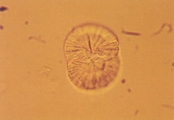

Рис. 1. Микрофотография сульфодиазинового кристалла в мочевом осадке 7-летнего кастрированного самца кота, которому применяли триметоприм-сульфадиазин орально (не окрашено, увеличение Х 250). |